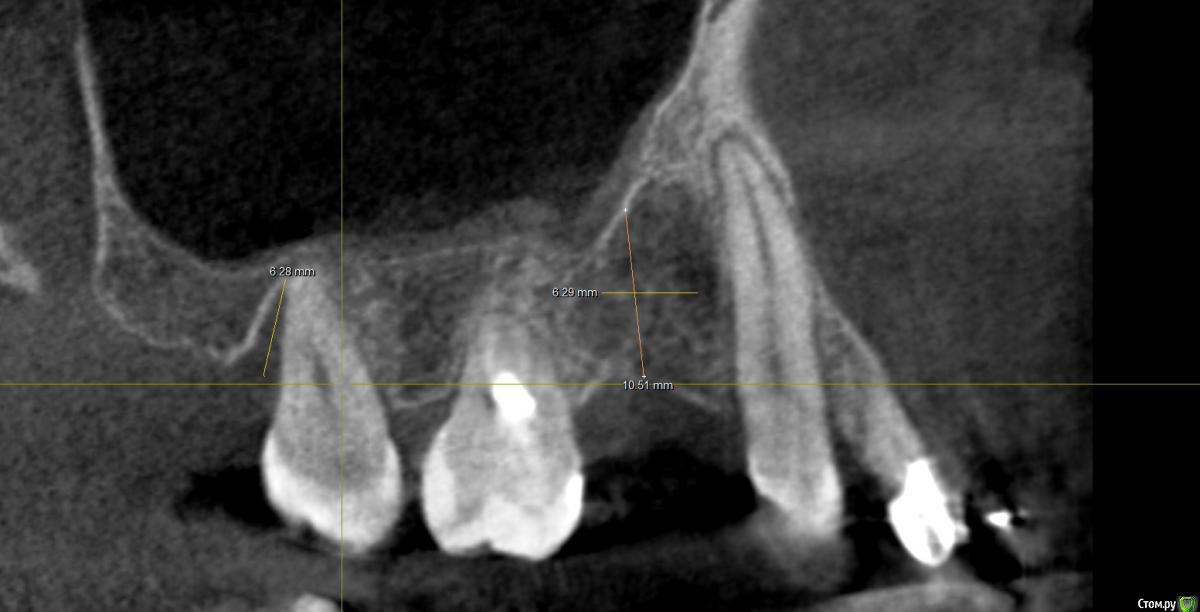

Al..ks Опубликовано 18 апреля, 2019 Поделиться Опубликовано 18 апреля, 2019 Добрый день. Планируется имплантация(15 или 14. брекеты ношу, поэтому не знаю какой будет)+аугментация (в области кармана 17 и при имплантации в случае недостатка кости)+пластика десны+установка формирователя. Все за раз.На выбор dentium, Astra, Nobel, Straumann. Подходят любые и выбор за мной(я склоняюсь к Астре). Правильный выбор? . Плюс ко всему по КТ там отсутствует кортикальный слой( по словам врача) я так понял с наружней стороны, поможет ли аугментация?И поможет ли она с карманом 17? И так как двигали зубы в области корня 11 появилась пустота (толи уже было)в середине лечения и на данный момент Надо ли делать резекцию корня - или канал перелечивать (там ставили СВШ перед брекетами) перед протезирование? Ссылка на комментарий

suballex Опубликовано 19 апреля, 2019 Поделиться Опубликовано 19 апреля, 2019 Добрый день. Планируется имплантация(15 или 14. брекеты ношу, поэтому не знаю какой будет)+аугментация (в области кармана 17 и при имплантации в случае недостатка кости)+пластика десны+установка формирователя. Все за раз.На выбор dentium, Astra, Nobel, Straumann. Подходят любые и выбор за мной(я склоняюсь к Астре). Правильный выбор?Правильный Плюс ко всему по КТ там отсутствует кортикальный слой( по словам врача) я так понял с наружней стороны, поможет ли аугментация?И поможет ли она с карманом 17?Аугментация с карманом не поможет. В остальном - да И так как двигали зубы в области корня 11 появилась пустота (толи уже было)в середине леченияи на данный момент Надо ли делать резекцию корня - или канал перелечивать (там ставили СВШ перед брекетами) перед протезирование?Нужно сравнить КТ начала лечения и последнее. Рентгенологически, канал 11 пролечен хорошо. Возможно, это остаточные явления. Ссылка на комментарий

Al..ks Опубликовано 19 апреля, 2019 Автор Поделиться Опубликовано 19 апреля, 2019 Правильный Аугментация с карманом не поможет. В остальном - да Нужно сравнить КТ начала лечения и последнее. Рентгенологически, канал 11 пролечен хорошо. Возможно, это остаточные явления.Спасибо за ответ. В отношении 17 мне планировали там подрезать десну (типо лучше будет возможность чистить и дольше зуб сохранить. Хотя думаю чувствительность поднимется блин(() и этот материал использовать для пластики десны у 16 и заодно подсыпать туда костного материала .Хотя когда еще давно (года три назад) удаляли 18 и чистили там грануляции, стенки между 17-18 не было.И там уже был этот карман и ничем закрыть его нельзя - пустая трата денег и кость вниз не нарастет. Хорошо хоть подвижность уменьшилась - наверное благодаря брекетам). Не нанесет ли вред аугментация зубу 17? Ссылка на комментарий